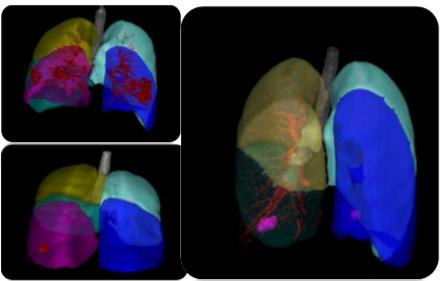

智能临床——聚焦重大疾病的GE医疗精准医学院:GE精准医学院成立于2018年,3年来自主研发出了多款辅助新冠肺炎、乳腺疾病、实体瘤等重大疾病诊疗的AI科研分析软件。在新冠疫情之中,GE医疗CT影像智能分析平台Lung Intelligence Kit(LK)通过AI分析对无症状病患和不易发现的新冠病灶进行智能识别并预测中后期复杂病变,同时打破设备限制,对不同型号的CT数据进行规范化处理。经过了近3个月的深度学习,LK已升级至2.2版本,拓展了新冠类别区分、肺部动静脉区分、提取智能分析影像学特征等功能更便于预后预测,整体深度学习数据量近5,000例,精准度 (AUC)达到95%,目前已在50家医院辅助科研。

LK 2.2版本:实现肺部动静脉区分